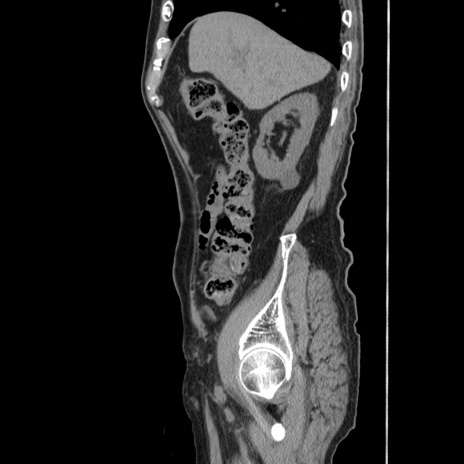

症例24(矢状断像)

【症例】80歳代男性

【主訴】左側腹部痛、嘔吐

【現病歴】本日早朝より左腹部に痛みあり。昼頃嘔吐認めたため、救急要請。

【既往歴】直腸癌(Mile手術)、胆摘

【身体所見】意識清明、BT 35.9℃、BP 221/93mmHg、SpO2 97%(RA) 、腹部:左ストーマ周囲に限局性の腹部膨隆あり。 膨隆部自発痛・圧痛あり・軟。

【データ】WBC 7700、CRP 0.09